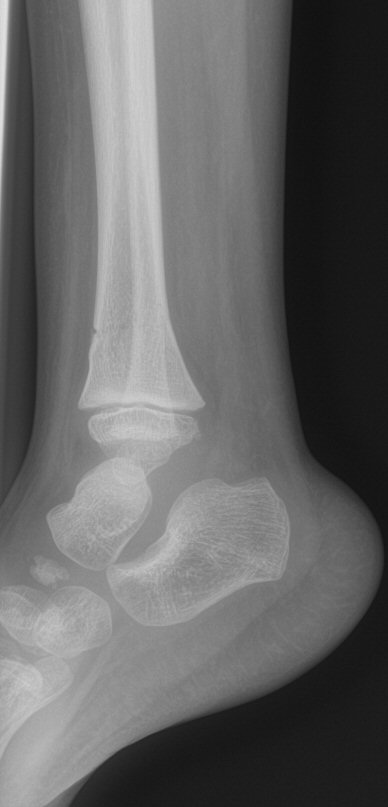

Distala tibiametafys- och fibuladiafysfrakturer. Behandlades icke-kirurgiskt.